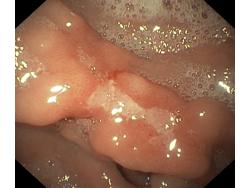

Wrzód trawienny